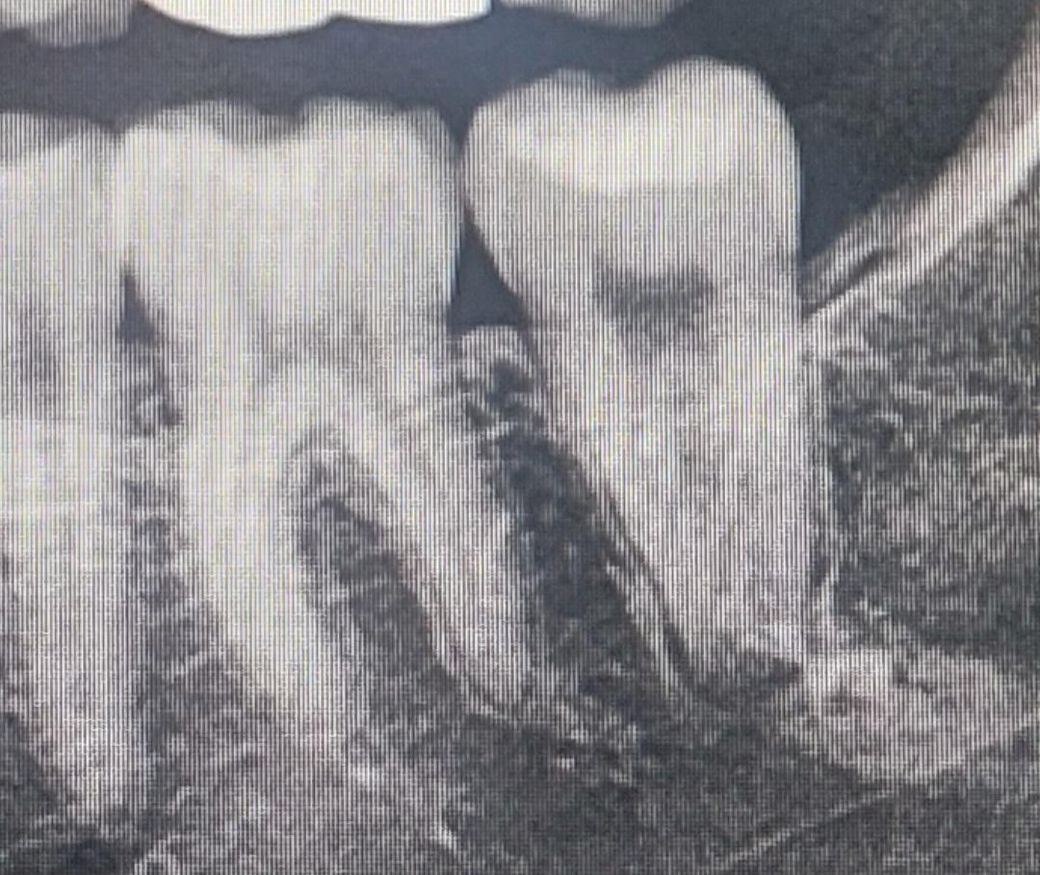

가장 끝 어금니 뿌리 부분이 까맣게 나와있는데 뿌리염증이거나 녹은 걸까요? 얼마전에 치과 다녀온 후 찍은 사진인데 의사 선생님께서는 별말 없으셨긴 한데 사진을 보니 좀 걱정되서요ㅠㅠ 그리고 잇몸이 자주 붓고 약해서 걱정인데 치석 안생기게 어떻게 잘 관리하나요?

해당치아의 주변 치주조직이 아주 건강해보이진 않습니다 염증도 약간 잡히고, 치주인대도 형태가 어지지하고요. 다만 바로 치료를 들어갈지는 좀 애매하네요